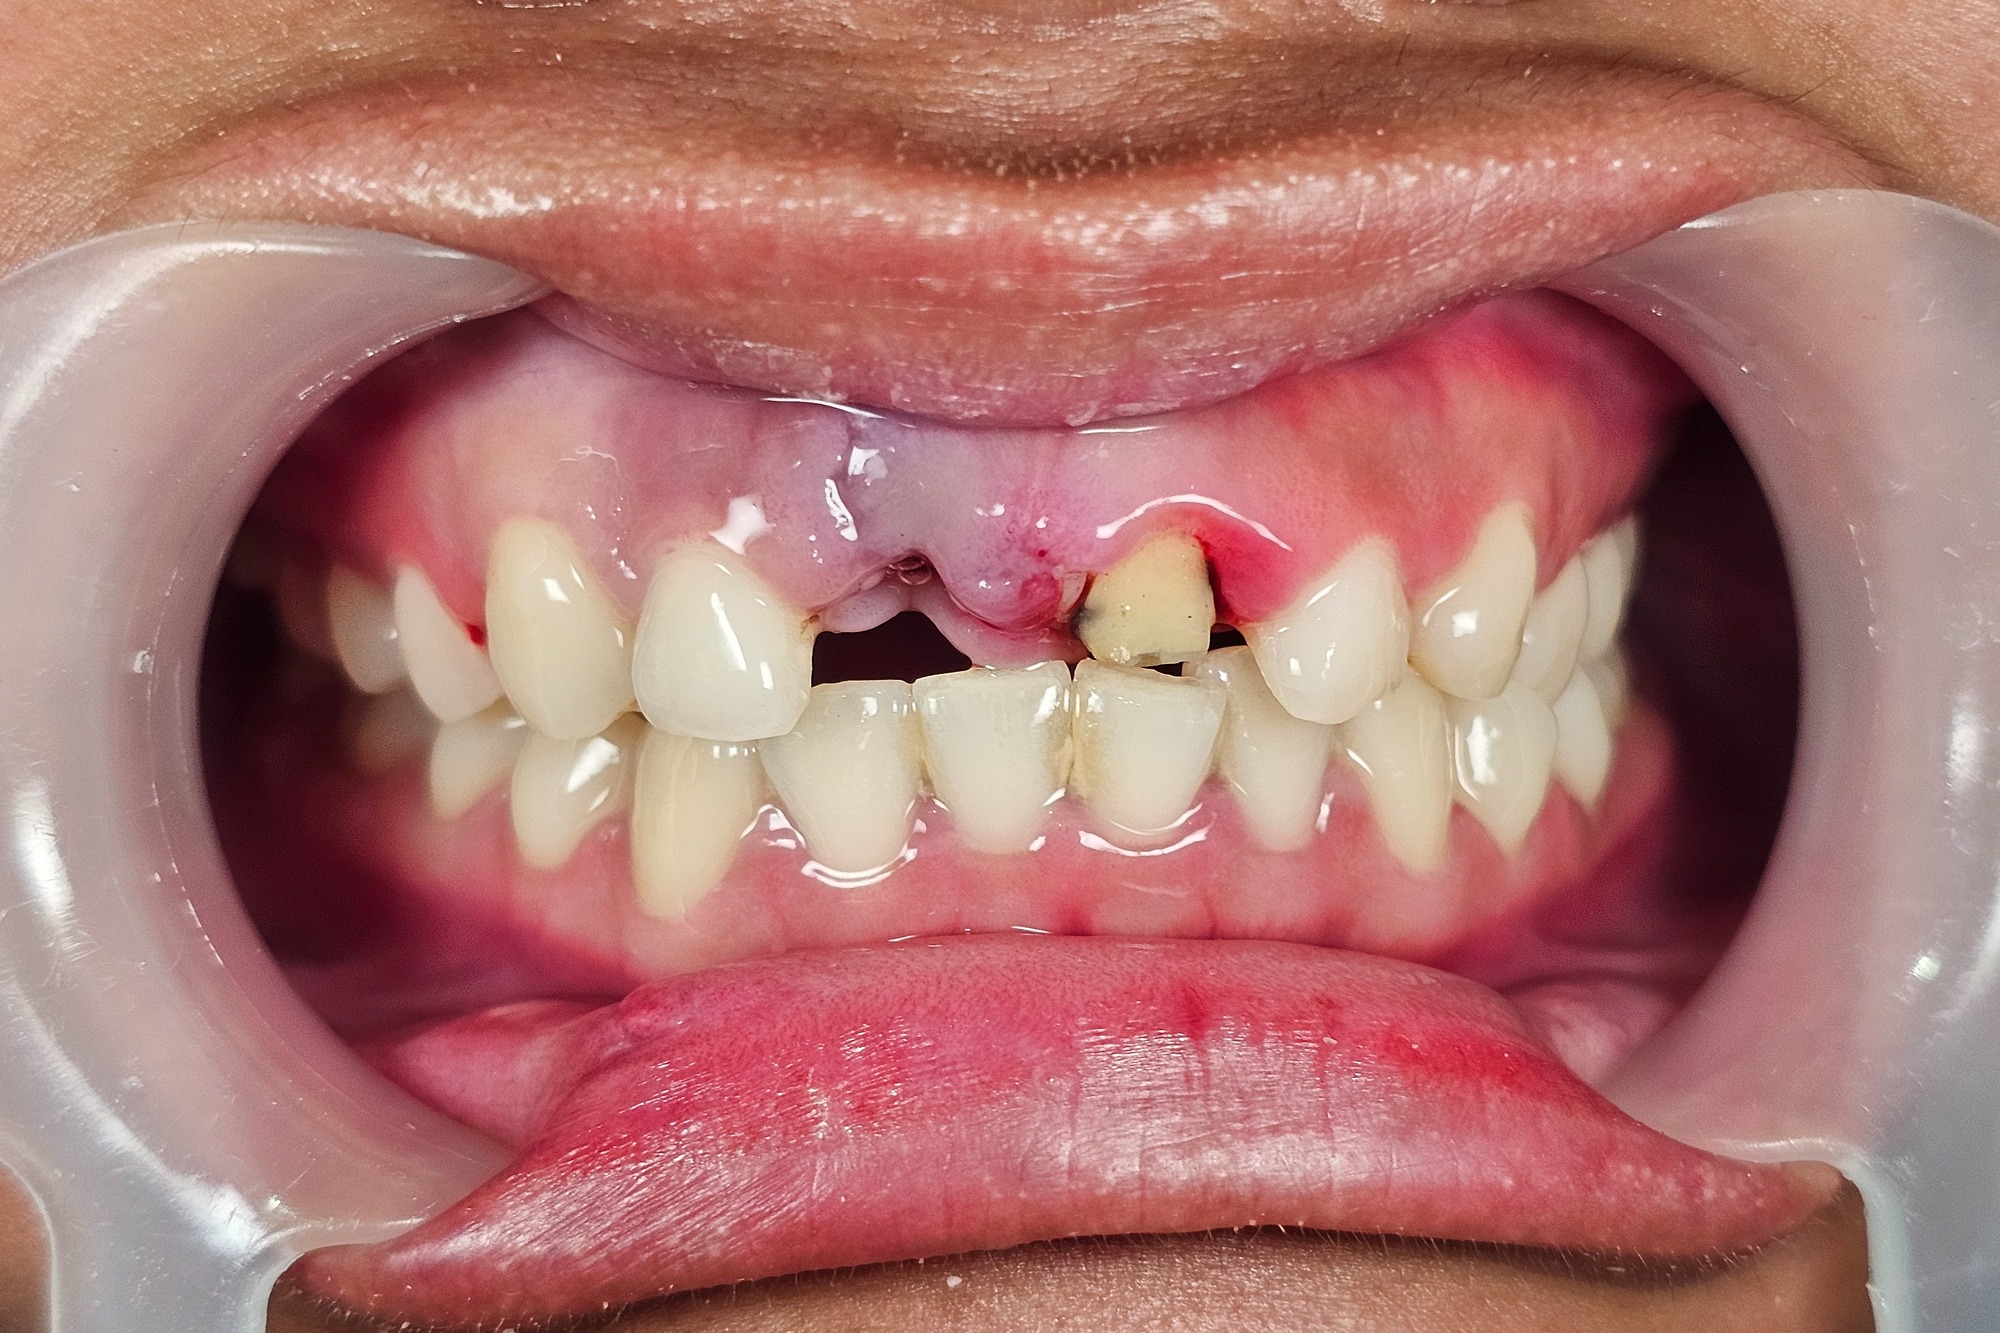

Layanan Maryland Bridge Pada kasus ini, pasien datang dengan kondisi kehilangan satu gigi…

Bridge gigi depan adalah salah satu pilihan perawatan untuk menggantikan gigi depan yang hilang. Perawatan ini dilakukan dengan cara memanfaatkan gigi di sebelah kiri dan kanan celah sebagai penyangga, lalu memasang gigi tiruan di tengahnya sehingga tampilan gigi kembali utuh.